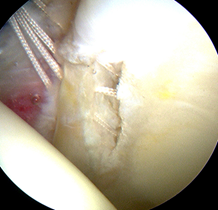

髋臼盂唇损伤因素包括创伤、退变、发育不良和髋关节撞击综合征(Femoroacetabular impingement syndrome ,FAI)。髋臼盂唇损伤后将改变髋关节的生物力学机制,引起髋部或腹股沟区疼痛,造成关节不稳,增加关节应力,最终导致骨性关节炎的发生。(左图:正常的盂唇;右图:盂唇撕裂)

在持续牵引下首先进入髋关节中央间室,在70度镜下进行关节探查,清理增生的炎性滑膜、取出游离体、处理软骨损伤及切除病变的髋臼盂唇;对于FIA患者,磨削骨性髋臼缘去除pincer撞击,如果不存在Pincer撞击,则仅需磨削髋臼缘去皮质化,新鲜化髋臼缘形成一个弧形的、光滑的渗血骨床。对损伤的盂唇尽量予以缝合(采用可吸收锚定)。然后在非牵引下进入外周间室,30度镜下对股骨头颈处的Cam撞击进行股骨头颈成型,避免修复的盂唇组织发生撞击。(左图:关节镜下缝合盂唇;右图:缝合后的盂唇)